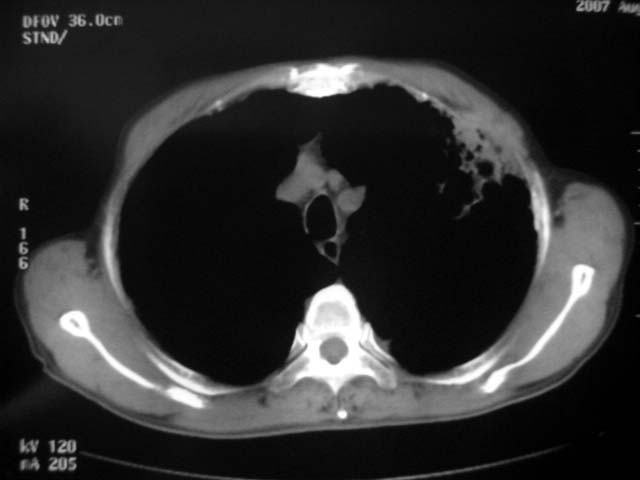

以下是引用zjzjr在2007-9-4 17:00:00的发言:[br]双上肺继发型结核伴左上肺空洞形成.慢性支气管炎伴肺气肿.

以下是引用liuzheng_9326在2007-9-4 16:23:00的发言:[br]痰检未见结核菌, 治疗后症状好转。图像符合陈旧性结核伴感染。